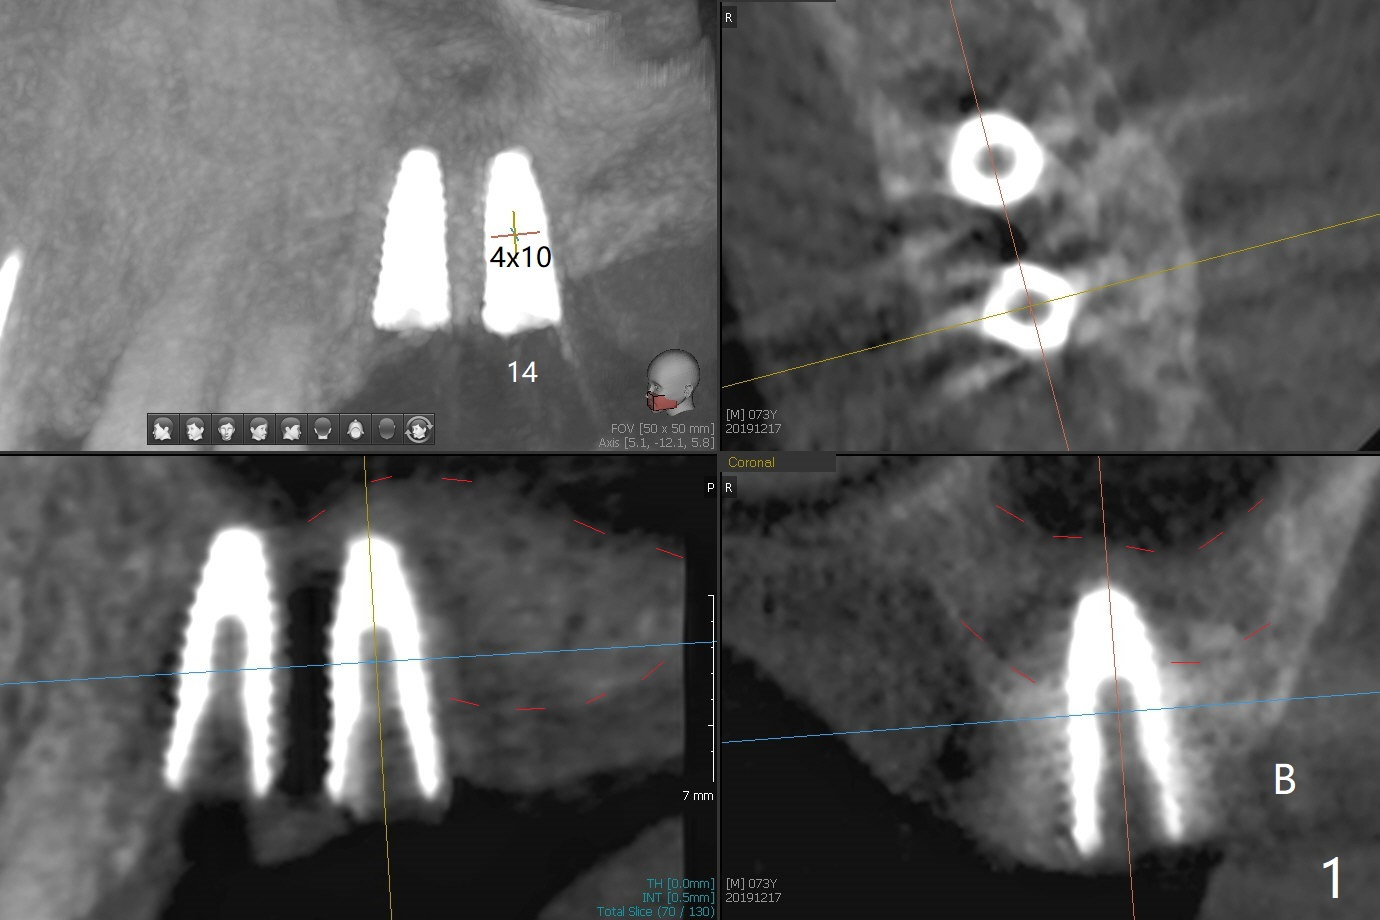

Three months post #14 implant removal and bone graft, the existing guide is reused, but no stop fixture mount cannot be inserted into #13 implant as an anchor. After 3.5x7.3 mm drill with 12 mm offset, the bottom of the osteotomy is not so hard; therefore sinus lift is conducted with allograft and 4x10 mm dummy implant (Fig.1). The lifted sinus floor is in fact not noted during the surgery (Fig.1 dashed red line). Sinus lift continues with bone graft and 4.5x10 mm (Fig.2); bone graft is squeezed out (*). The final implant (5x8.5 mm) is not seated until use of 4.5x7.3 and 4.0x10 mm drills (Fig.3). The implant is further placed free hand until subcrestal distal; since the torque is not high, a healing screw (S) is placed with packing allograft around the plateau of the implant (*). By placing a 4.5x4.5(4) mm cemented abutment at #13, a provisional is fabricated with extension to cover the bone graft at #14. When the provisional dislodges 1.5 months postop, #14 wound does not heal with the erythematous gingiva and exposed healing screw (Fig.5). Diabetes is not well controlled (HbA1c >6% (normal 4-5.6%)). Poor oral hygiene is another contributing factor in failure. After cleaning and torque 30 Ncm of the abutment at #13, impression is taken. In fact the tooth #12 has lost the palatal cusp (Fig.6 <); a crown will be fabricated at #12 when the implant at #14 osteointegrates. The implant at #14 is uncovered 5 months postop (Fig.7 (6.8x3 mm healing abutment)). The implants of #13 and 14 are close to each other, which is related to the slanted ridge at #13 (^). The osteotomy and the implant slide distal during placement (arrow). The implant in the slanted ridge should be intentionally placed mesial to compensate for the shifting. Or the ridge should be trimmed precisely; open surgery is necessary. A 5.2x5.5(4) mm cemented abutment is apparently completely seated with 35 Ncm torque 6 months postop (Fig.8). Although the distal plateau of the implant is exposed when the provisional is removed, post cementation bitewing shows equicrestal placement distal (Fig.9).